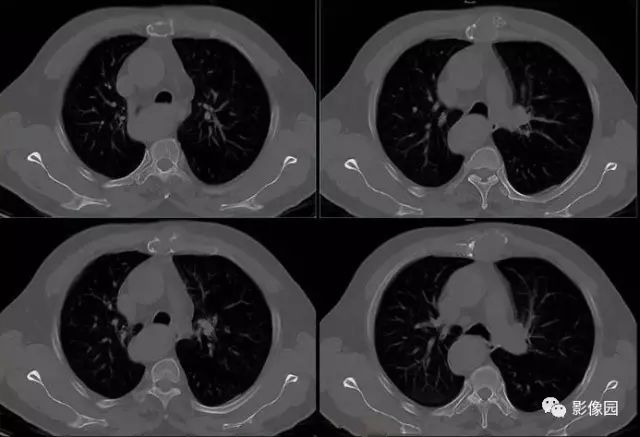

胸骨浆细胞骨髓瘤1例CT影像表现

【基本资料】男,66岁

【主诉】发现胸骨隆起1年余

【现病史】患者于1年前发现胸骨局部隆起,无红肿热痛,当时未予治疗,近来自觉隆起明显增大,伴胸前区隐痛不适。

【专科检查】胸骨上段局部隆起,压痛明显,胸部呼吸运动正常

肚肚丫头: 胸骨体局部呈膨胀性骨质吸收破坏,内呈软组织密度影,可见点状钙化,增强扫描呈轻度强化,周围软组织略肿胀。考虑:1.骨巨细胞瘤;2.浆细胞瘤;3.嗜酸性肉芽肿

【病理结果】(胸骨占位)符合浆细胞骨髓瘤

CT表现:特征性穿凿状、鼠咬状及蜂窝状骨破坏,边缘清楚,骨质疏松,病理性骨折及软组织肿块等表现,骨质硬化及骨膜反应少见。

骨破坏区完全为软组织取代,骨质膨胀,边界清楚,常突破骨皮质形成软组织肿块。增强扫描可见病灶轻中度强化,一般于静脉期达峰值。